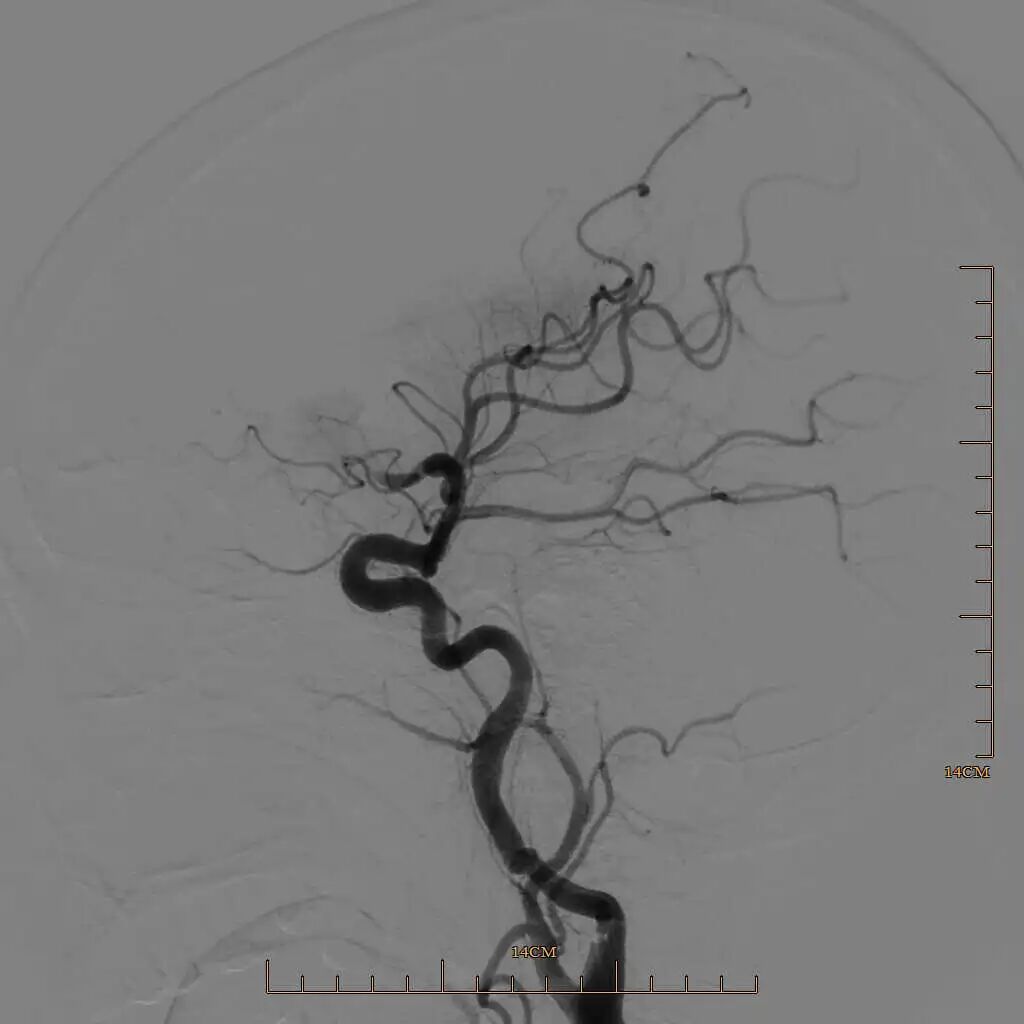

90cm Locaste 088输送导管建立路径,造影提示左侧大脑中动脉M1段闭塞。

动脉长鞘怎么置入有励可说|Locaste 088励楷长鞘及Tarvos微导丝在左侧大脑中动脉闭塞取栓术中的应用_https://www.jmylbn.com_新闻资讯_第8张

动脉长鞘怎么置入有励可说|Locaste 088励楷长鞘及Tarvos微导丝在左侧大脑中动脉闭塞取栓术中的应用_https://www.jmylbn.com_新闻资讯_第9张

动脉长鞘怎么置入有励可说|Locaste 088励楷长鞘及Tarvos微导丝在左侧大脑中动脉闭塞取栓术中的应用_https://www.jmylbn.com_新闻资讯_第10张

取栓后下干再通,上干仍闭塞。

动脉长鞘怎么置入有励可说|Locaste 088励楷长鞘及Tarvos微导丝在左侧大脑中动脉闭塞取栓术中的应用_https://www.jmylbn.com_新闻资讯_第13张

动脉长鞘怎么置入有励可说|Locaste 088励楷长鞘及Tarvos微导丝在左侧大脑中动脉闭塞取栓术中的应用_https://www.jmylbn.com_新闻资讯_第14张

半回收取栓支架取栓后大脑中动脉上干血管再通。

动脉长鞘怎么置入有励可说|Locaste 088励楷长鞘及Tarvos微导丝在左侧大脑中动脉闭塞取栓术中的应用_https://www.jmylbn.com_新闻资讯_第18张

动脉长鞘怎么置入有励可说|Locaste 088励楷长鞘及Tarvos微导丝在左侧大脑中动脉闭塞取栓术中的应用_https://www.jmylbn.com_新闻资讯_第19张

动脉长鞘怎么置入有励可说|Locaste 088励楷长鞘及Tarvos微导丝在左侧大脑中动脉闭塞取栓术中的应用_https://www.jmylbn.com_新闻资讯_第20张

动脉长鞘怎么置入有励可说|Locaste 088励楷长鞘及Tarvos微导丝在左侧大脑中动脉闭塞取栓术中的应用_https://www.jmylbn.com_新闻资讯_第21张